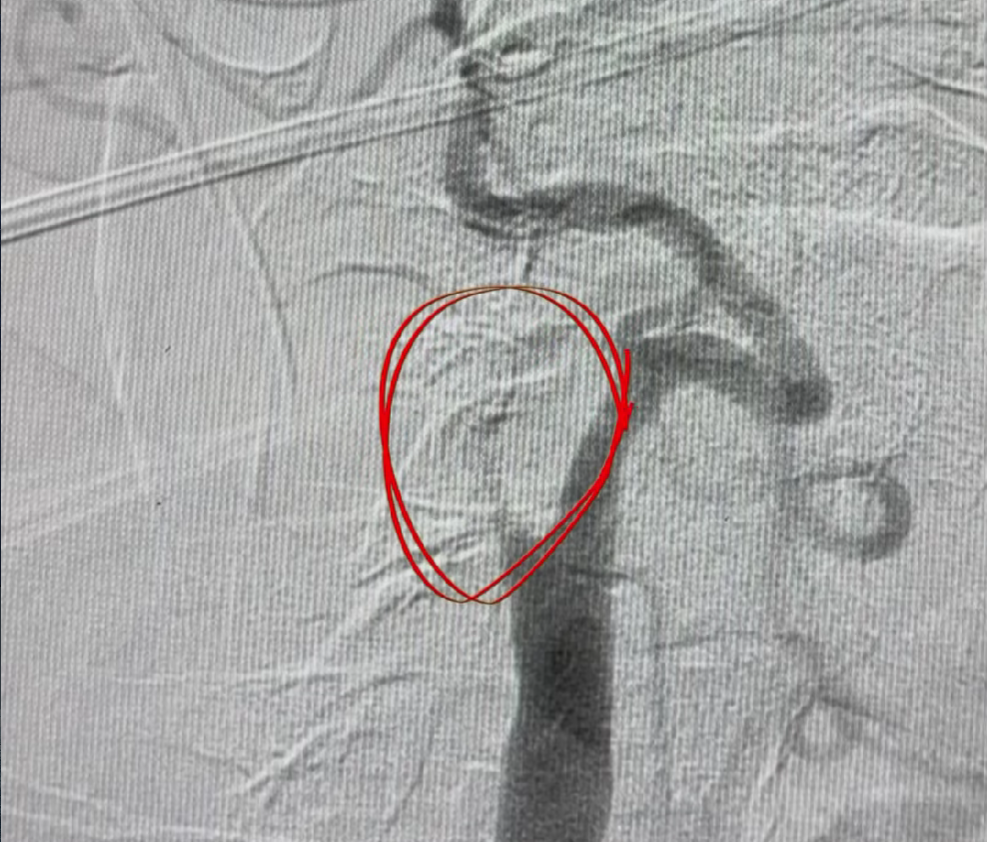

Yana bir shunday murakkab amaliyot klinikamizning intervension kardiojarrohlari tomonidan muvaffaqiyatli amalga oshirildi. Bu kabi operatsiyalar zamonaviy texnologiyalar, chuqur bilim va katta tajribani talab qiladi. Har bir harakat aniqlik bilan bajariladi, har bir qaror esa bemorning sog‘lig‘i va hayoti uchun muhim ahamiyatga ega.

Еще одна сложная операция была успешно проведена нашими интервенционными кардиохирургами. Подобные вмешательства требуют не только современных технологий, но и глубоких знаний, большого опыта и абсолютной точности в каждом действии.